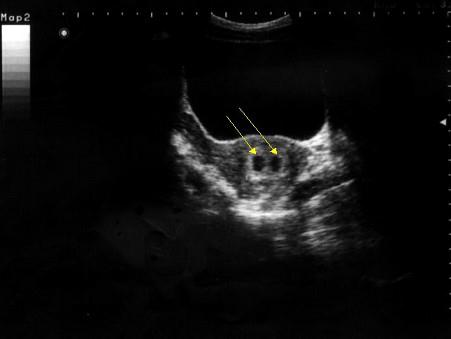

超声检查如图,最可能的诊断是 ( )A、子宫肌瘤B、早孕并双胎妊娠C、宫颈囊肿D、早孕并宫腔积液E、早孕

选项 A、子宫肌瘤 B、早孕并双胎妊娠 C、宫颈囊肿 D、早孕并宫腔积液 E、早孕

答案 B